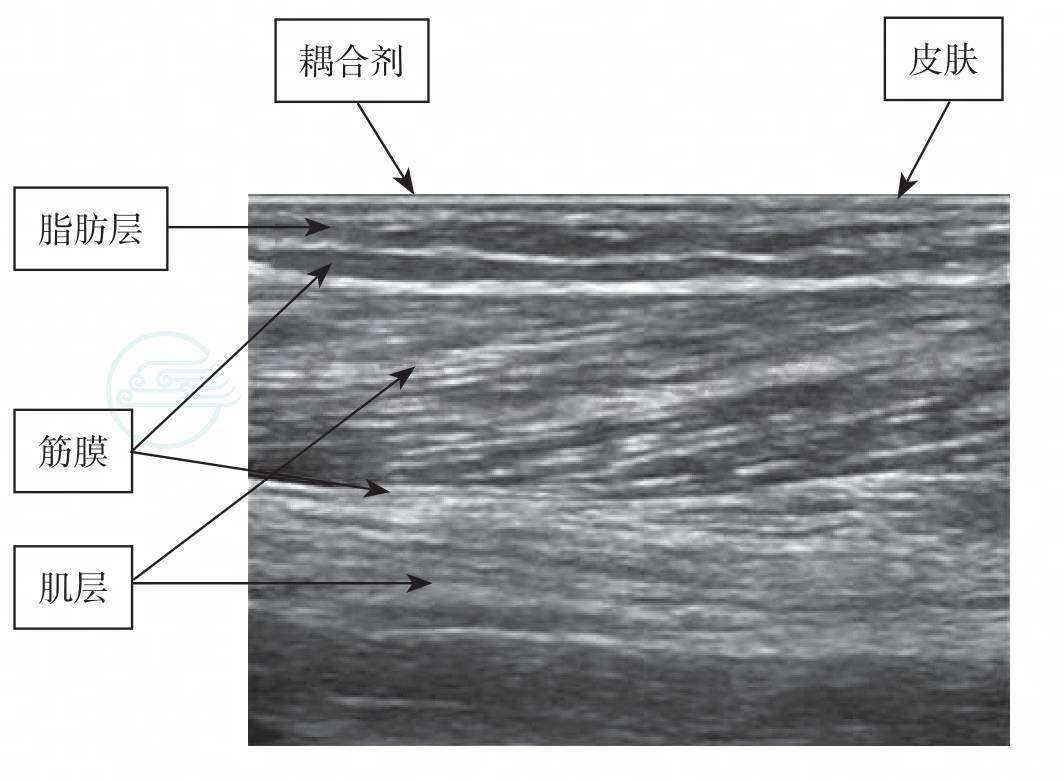

八、正常软组织的超声表现(图8-1)

皮肤:高回声带。

脂肪组织:皮下呈低回声。

纤维组织:与其他组织交错分布呈强回声。

肌肉组织:长轴呈纹状,短轴呈斑点状。

血管:呈无回声管道。

骨骼:骨皮质呈强回声带,后有声影。

图8-1 浅表组织结构超声图